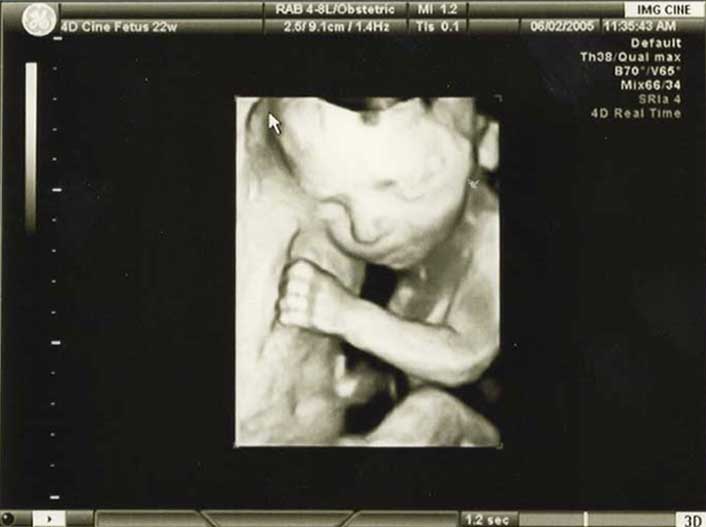

3D/4D HD LIVE

Στο ιατρείο μας προσφέρουμε υψηλής ευκρίνειας 3D και 4D τεχνολογία απεικόνισης του εμβρύου. Η τεχνολογία αυτή αποτελεί ένα ακόμα σημαντικό διαγνωστικό όπλο στη φαρέτρα του προγεννητικού ελέγχου, ενώ ταυτόχρονα ενισχύει την ανάπτυξη του δεσμού ανάμεσα στους μελλοντικούς γονείς και το μωρό τους.